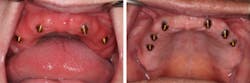

Fixed implant-supported bridges are becoming more prevalent worldwide. There are multiple types of bridges available, but all are expensive, and they require advanced clinical skills. Although these fixed bridges are a wonderful service to offer, we should remember the value of removable implant-retained dentures (figure 1). Attachments, such as Locator by Zest and Equator by Rhein83, have many benefits. They are the most affordable, least complicated, easiest to repair, and easiest to clean full-arch implant option.

It is widely noted that a minimum of two implants are required in the mandible for removable dentures.5 Four or more implants are optimal for the maxilla.6 These minimums can be successful more than 85% of the time, but long-term success can be increased by adding additional implants (figure 4).7 Balaguer et al. studied 95 patients over an average of six to nine years and found that survival rate in the maxilla of four implants was 85.7%. Survival rate of six implants was 100%. In the mandible, survival rate of two implants was 96.6%, whereas survival rate for three implants was 100% and survival rate for four implants was 99%.7